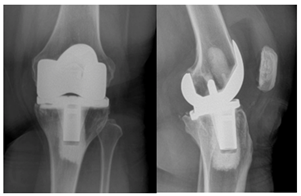

Prior to the patient’s chosen surgical date, she twisted her leg, felt a shift in her knee, and had severe pain along with the sensation her knee being locked (Figure 5).

She was taken to the operating room the following day. Her polyethylene was found in the suprapatellar pouch with damage particularly to the posterior medial region (Figure 6). The tibia tray was found to be well fixed but was found to be fractured in the posterior medial corner (Figure 7). Both component revision was undertaken using Zimmer® NexGen® RH knee with cemented stems as well as a trabecular metal femoral cone in the metaphysis (Figure 8).

Figure 5 AP/Lateral Left Knee showing metal on metal articulation of the femur on the tibia, disengaged polyethylene in the suprapatellar pouch as well as fracture of the posterior medial corner of the tibia tray.

Figure 8 AP/Lateral femur/Lateral tibia of the left knee following revision to a rotating hinge knee with cemented stems and femoral metaphysical cone.